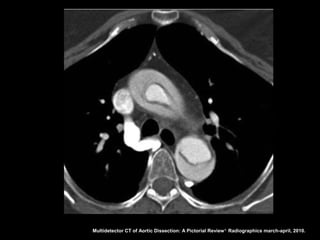

Dissecção aórtica

Angiotomografia

Diagnóstico: identificação do flap intimal, que se

apresenta como uma fina membrana separando a

luz falsa da verdadeira;

Sensibilidade e especifidade acima de 95% na

detecção do flap intimal;

Após diagnóstico: localizar, definir envolvimento de

ramos aórticos e identificar fatores agravantes

relacionados à própria aorta.

Multidetector CT of Aortic Dissection: A Pictorial Review 1. Radiographics march-april, 2010.